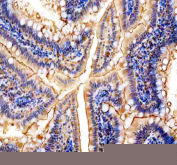

IHC staining of FFPE mouse colon tissue with NMU antibody, HRP-secondary and DAB substrate. HIER: boil tissue sections in pH8 EDTA for 20 min and allow to cool before testing.